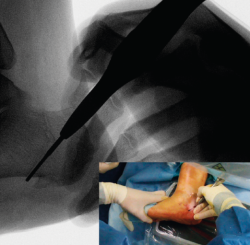

Una vez completada, se desplaza la tuberosidad del calcáneo manualmente en la dirección necesaria para la corrección de la deformidad y se introduce un periostotomo a través de la incisión en el escalón que queda tras el desplazamiento para aumentar y mantener dicho desplazamiento. En caso de pie plano valgo, el desplazamiento es medial y se introduce el periostotomo en dirección anterior en la esponjosa del cuerpo del calcáneo para aumentar la traslación (Figuras 7 y 8). En caso de pie cavo varo, el desplazamiento es lateral y se introduce el periostotomo en la esponjosa de la tuberosidad.

Figura 7. Imagen fluoroscópica de la traslación de la tuberosidad con un periostotomo (imagen anteroposterior) y su correspondencia en cirugía.

Se debe mantener la rodilla flexionada para evitar que la tensión del Aquiles nos limite el desplazamiento.

Figura 8. Imagen fluoroscópica de la traslación de la tuberosidad con un periostotomo (imagen axial) y su correspondencia en cirugía.